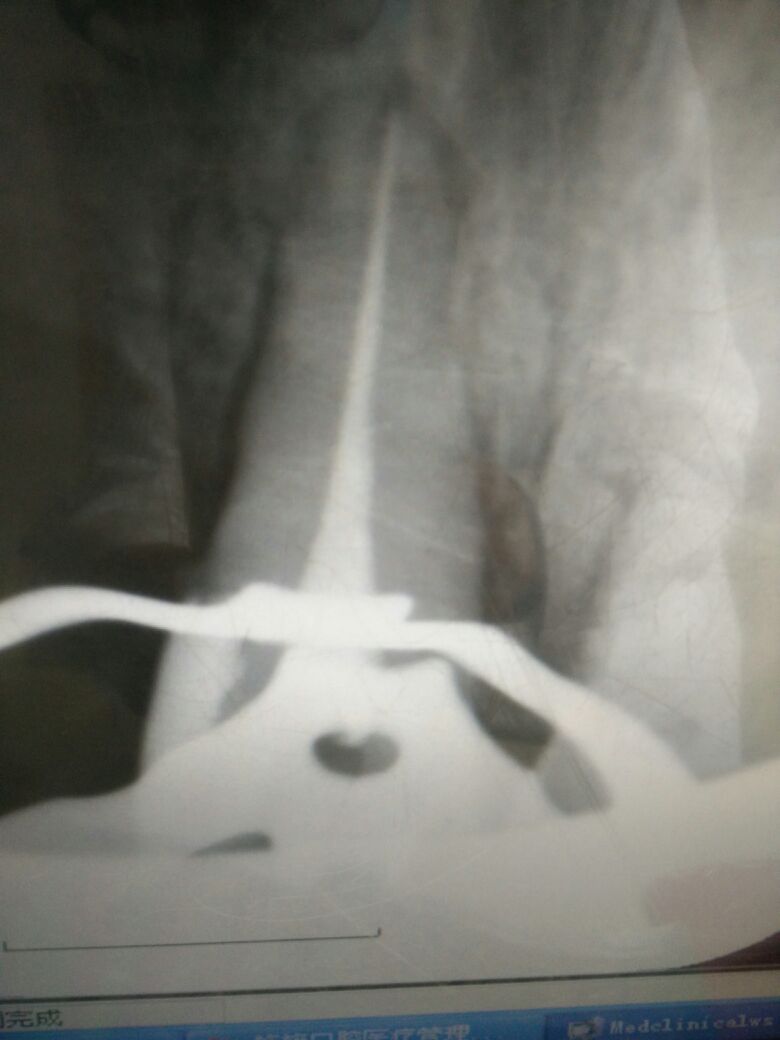

X-ray显示根管治疗不完善。

2.一次性根充后临时桩冠修复,观察两周。

感谢分享~资料图片比较完善,试尖片和根充片都有。目前临床多采用纤维树脂桩核修复,在充分考虑剩余牙体组织抗力的前提下,要尽可能扩大桩核的粘结面积